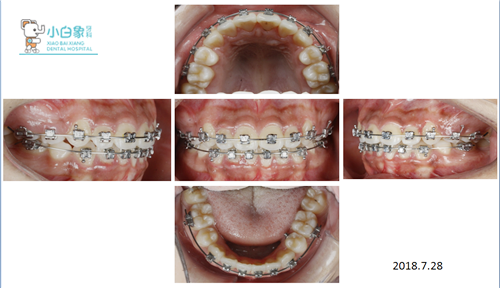

治疗过程

粘全口直丝弓矫治器

更换12、14、16、18镍钛圆丝排齐牙齿

依次换16*22、18*25镍钛方丝整平牙弓

转儿牙拔除上颌多生牙(2017.3.11)